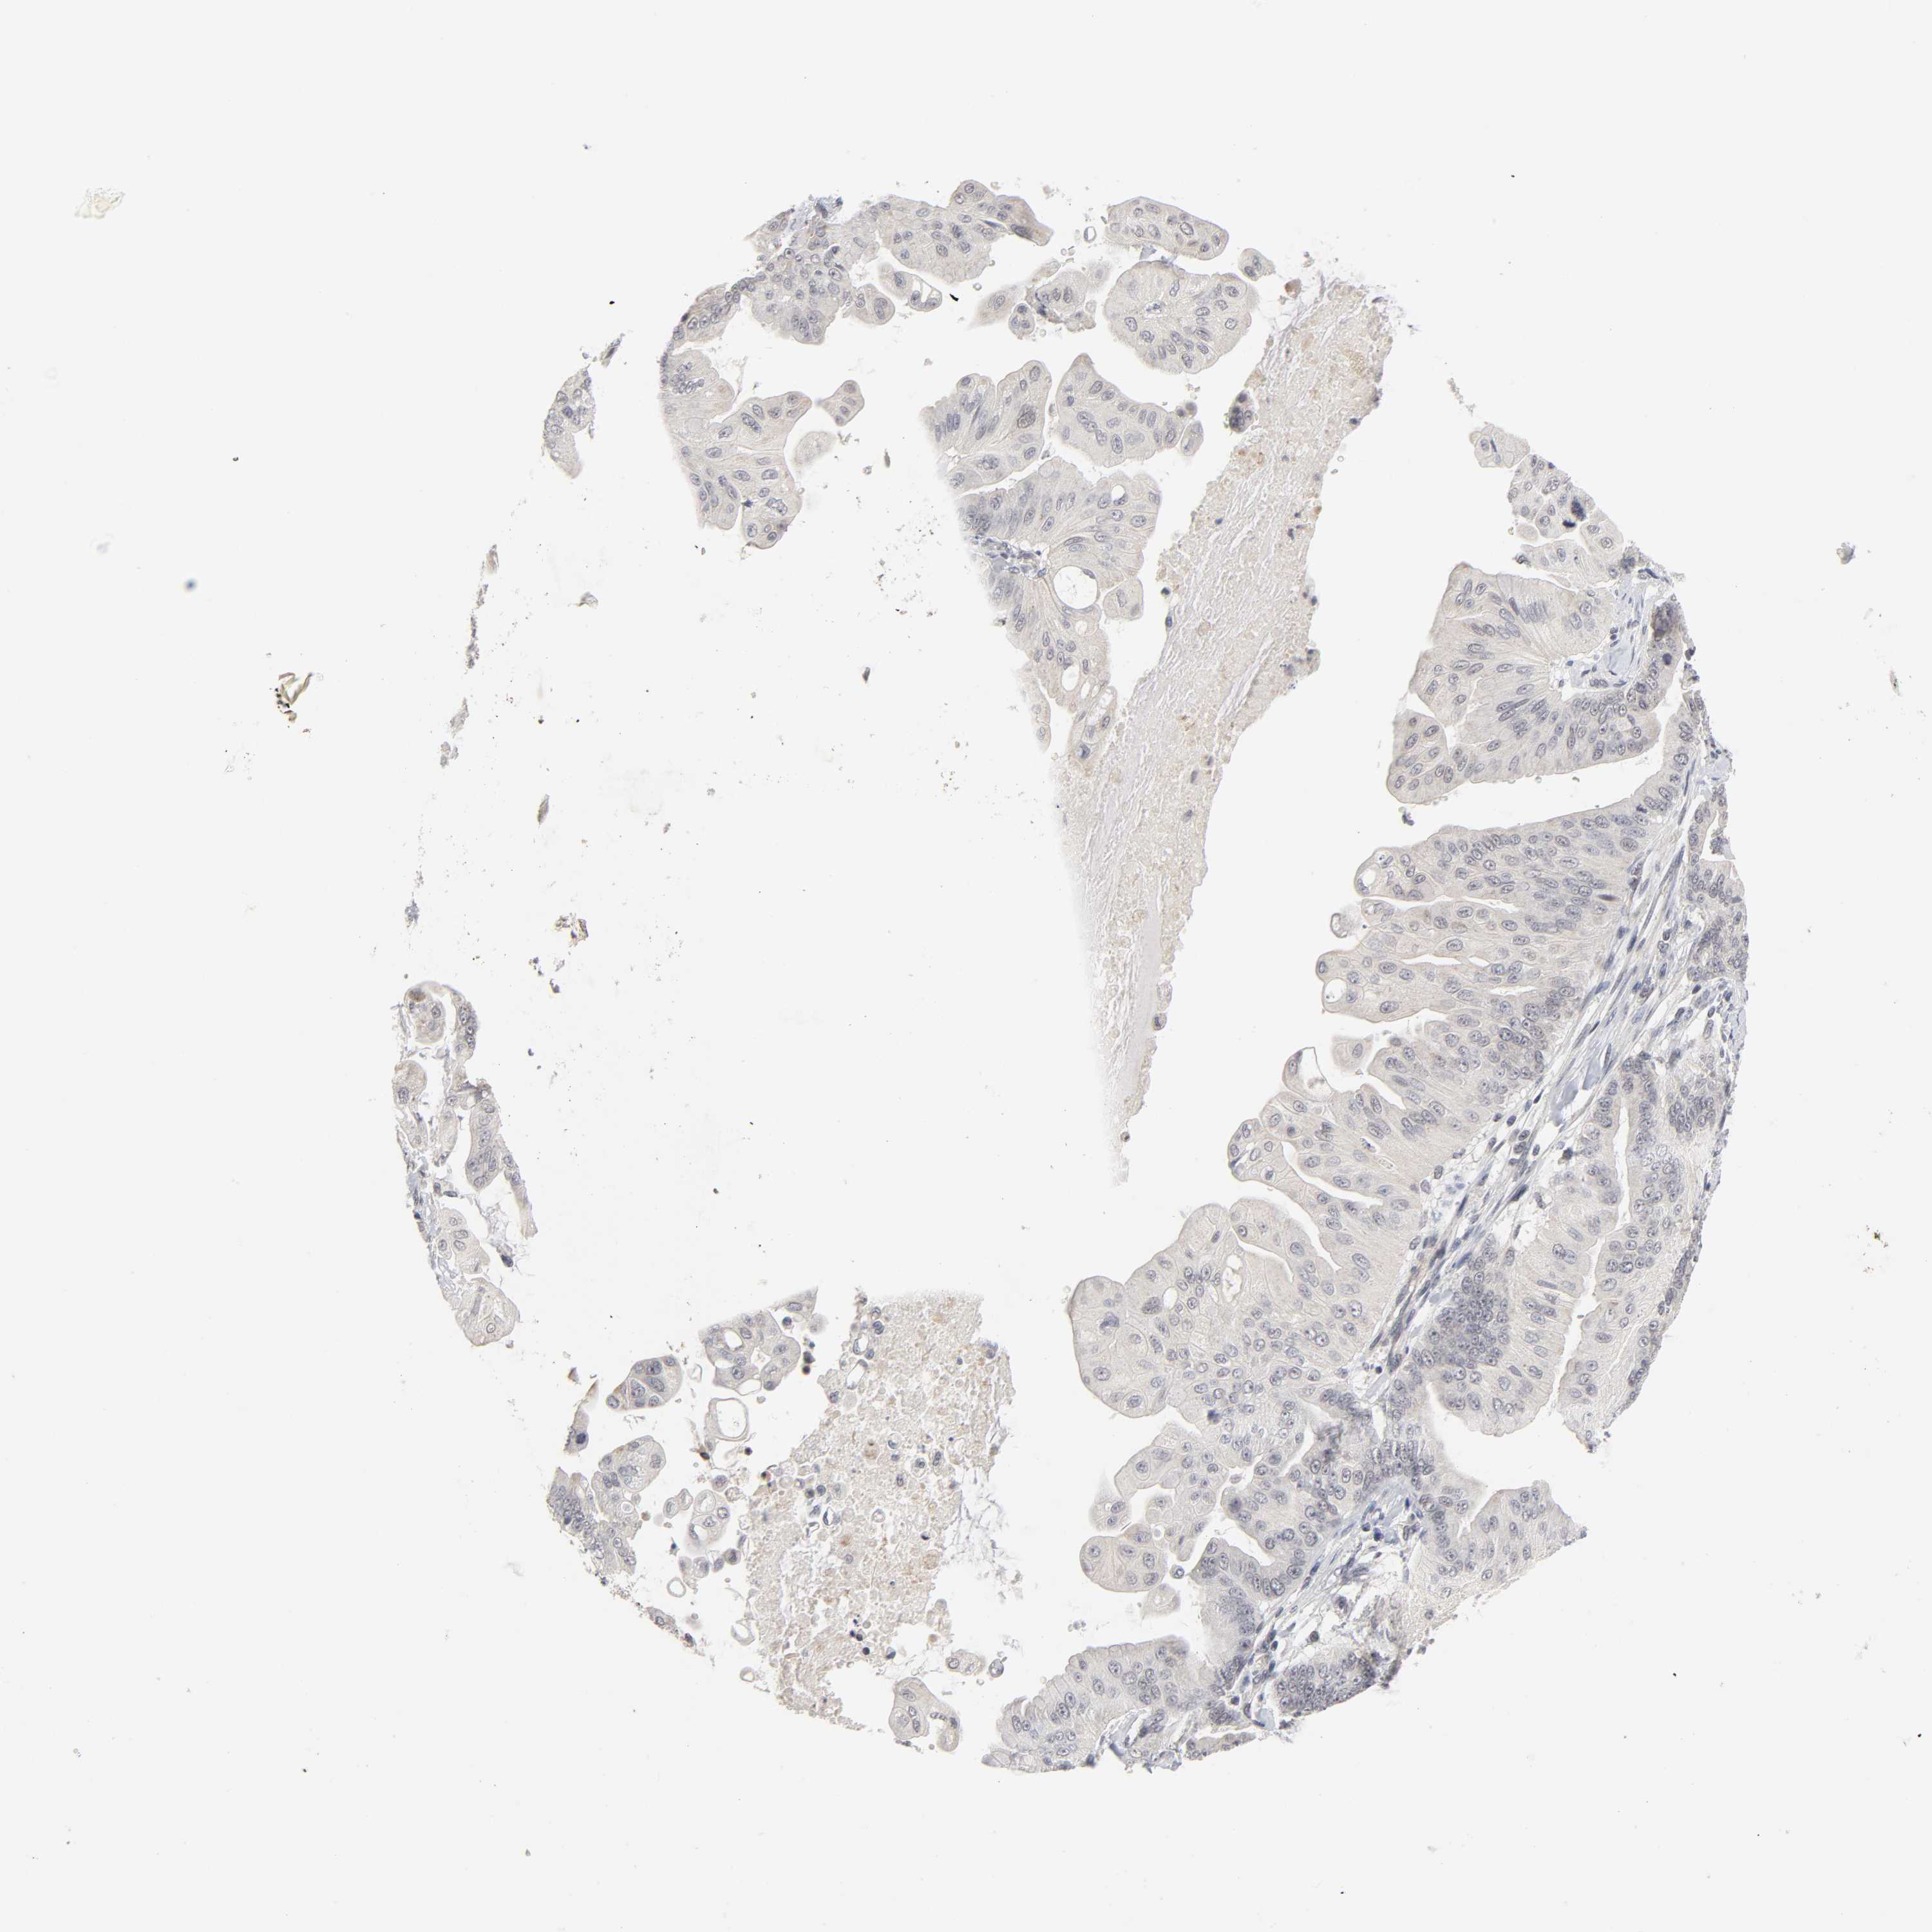

PANCREATIC CANCER - Protein expressioni

A mouse-over function shows sample information and annotation data. Click on an image to view it in a full screen mode. Samples can be filtered based on level of antibody staining by selecting one or several of the following categories: high, medium, low and not detected. The assay and annotation is described here.

Note that samples used for immunohistochemistry by the Human Protein Atlas do not correspond to samples in the TCGA dataset.

Antibody stainingi

Antibody staining in the annotated cell types in the current human tissue is reported as not detected, low, medium, or high, based on conventional immunohistochemistry profiling in selected tissues. This score is based on the combination of the staining intensity and fraction of stained cells.

Each image is clickable and will lead to virtual microscopy that enables deeper exploration of all samples and also displays staining intensity scores, fraction scores and subcellular localization as well as patient and tissue information for each sample.

Antibody HPA004171

Staining

High

Medium

Low

Not detected

Intensity

Strong

Moderate

Weak

Negative

Quantity

>75%

75%-25%

<25%

None

Location

Nuclear

Cytoplasmic/membranous

Cytoplasmic/membranous,nuclear

Adenocarcinoma, NOS

Adenocarcinoma, metastatic, NOS